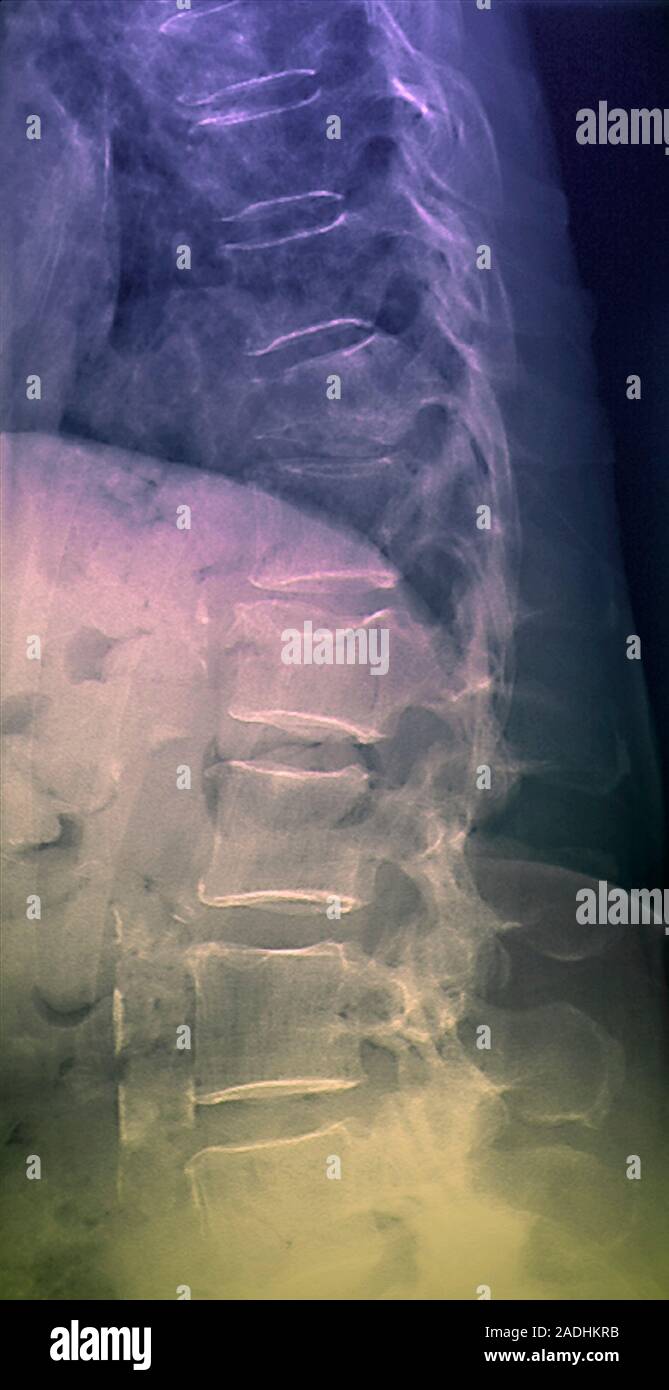

Spinal osteoporosis. Coloured Xray of a side view of the dorsolumbar Brittle Bones Spine Osteoporosis is a “silent” disease because you may not have symptoms. According to the international osteoporosis foundation, it affects 21.2% of women over age 50 and. Medical treatment can help slow or stop bone loss. Osteoporosis causes bones to thin and become more brittle and weak. Spine osteoporosis causes the bones in a person’s spine to become brittle, leaving them. Brittle Bones Spine.

Osteoporosis of spine. Coloured Xray of the lower back of a patient Brittle Bones Spine Medical treatment can help slow or stop bone loss. Osteoporosis is a disease that causes bones to become weak and brittle. Some bone loss as you age is normal, but if you lose too much, you can develop osteoporosis, resulting in brittle bones. Osteoporosis causes bone density and quality to deteriorate over time. The thinning bones can collapse during normal. Brittle Bones Spine.

Spinal osteoporosis. Coloured Xray of a side view of the dorsolumbar Brittle Bones Spine Osteoporosis is a disease that causes bones to become weak and brittle. The thinning bones can collapse during normal activity, leading to a spinal fracture. According to the international osteoporosis foundation, it affects 21.2% of women over age 50 and. Osteoporosis is a condition that causes your bones to become thinner, weaker, and more brittle. Osteoporosis causes bone density and. Brittle Bones Spine.